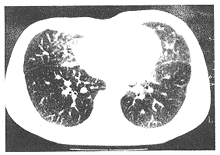

图2 肺泡微结石症CT片

双肺野纹理增粗,密度增高,呈网结带状改变,斑片状密度增高影,双肺门弥漫性病变.

胸部正位片:双肺见粟粒状颗粒,中内带尤著(图1)。肺CT:双肺野纹理增多、增粗,呈网结带状改变,可见斑片密度增高影,边缘模糊,未见明显块影形成,左下肺及右侧纵隔胸膜可见钙化影,纵隔内未见肿大的淋巴结。双肺门弥漫性病变,以间质为主(图2)。小儿支气管镜检查:声门隆突形状如常,气管粘膜无明显充血、水肿,所见支气管段以上无明显病变。右肺下叶通过支气管肺活检部分组织,并刷检涂片,灌洗液送检。灌洗液涂片见多量淋巴等圆形细胞及钙盐颗粒,未见肿瘤细胞(图3)。肺组织镜检:支气管粘膜水肿,慢性炎症改变,少量肺实质中见肺泡中钙盐沉着,未见结核及肿瘤,病理诊断为肺泡微结石症。

肺泡微结石症X线表现为弥漫性极细小的粟粒状阴影,全肺野密度增加,可分为点状、线状影,被称之为沙暴或雪暴[5],以双下肺野为著,不易与粟粒型肺结核鉴别。肺泡微结石症X线表现典型而临床症状轻微是诊断的重要依据[6]。值得注意的是患者多有结石咳出史,最严重并发症为肺动脉高压和肺心病[2],心脏增大,肺动脉略突出[7]。肺部高分辨CT(HRCT)表现为肺部遍布细点状钙化影,大小稍有差别,病灶向上向下逐渐增多,且以后下部最为密集。部分支气管壁不规则增厚,沿胸壁纵隔及膈面有较多胸膜钙化。心脏周围、膈肌结石沉着较多,说明活动度大的部位,结石沉着较多[8]。本例患儿心脏周围结石亦较其他部位为多。

肺泡微结石症的钙化微粒主要位于小叶内,伴发间质性气肿改变,与其他弥漫性病变HRCT表现不一样,所以HRCT对本病诊断及鉴别诊断起决定性作用[9]。肺功能早期无变化,进展期半数出现弥散功能低下,末期发展至明显限制性通气功能障碍,低氧血症为主[5]。本例患儿已出现限制性通气障碍,轻度低氧血症的表现。